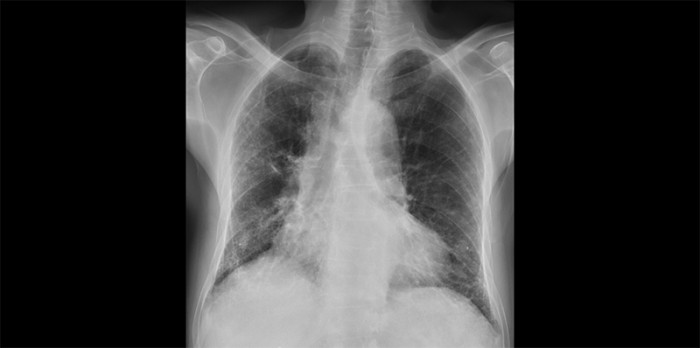

Vroegtijdige herkenning is belangrijk bij longfibrose

Longfibrose is zeldzaam en wordt dikwijls pas laat herkend, wanneer er vaak al substantiële longschade opgetreden is. Het is belangrijk dat huisartsen longfibrose vroegtijdig herkennen, want nieuwe therapeutische mogelijkheden kunnen achteruitgang van de longfunctie in een eerder stadium remmen. Aan de hand van een casus beschrijven wij de diagnostiek van longfibrose.